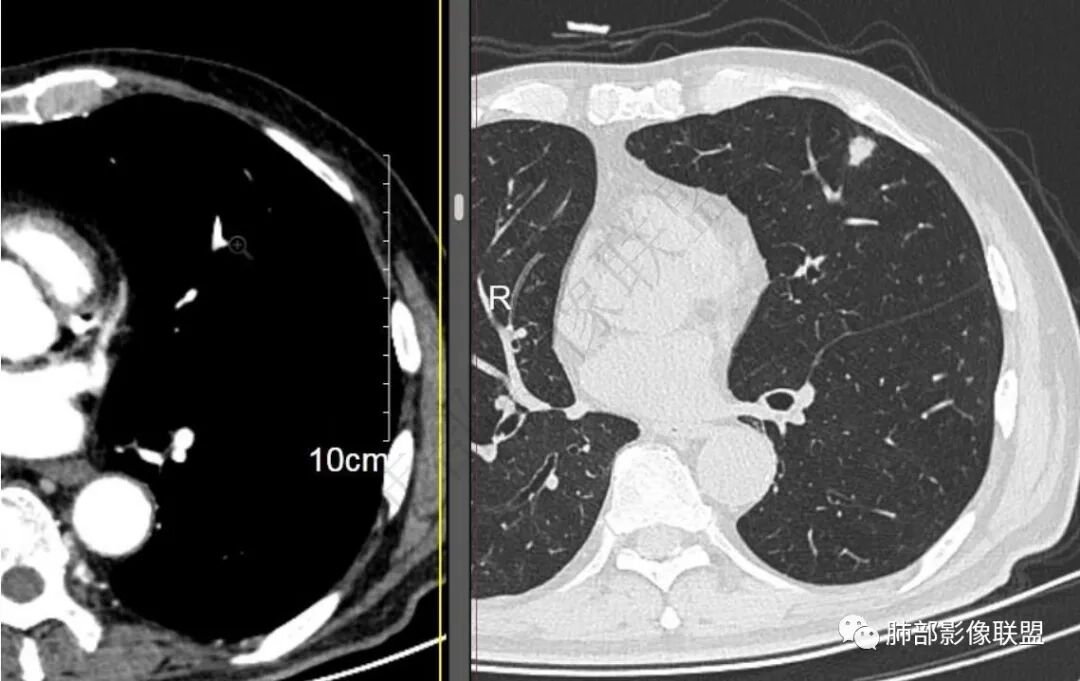

二..发现左肺上叶舌段实性密度小结节影,不规则略呈半环形,边界清楚,未见分叶、毛刺及磨玻璃晕。未见卫星病灶。

9个月后病灶明显增大,边缘较平直,部分膨隆,锁扣样外观,仍旧缺乏典型深分叶及张力,未见胸膜凹陷。

再1个多月后病灶继续增大,较明显不均匀强化,肺门一侧见低密度区。病灶边缘相对不清,可见毛刺。